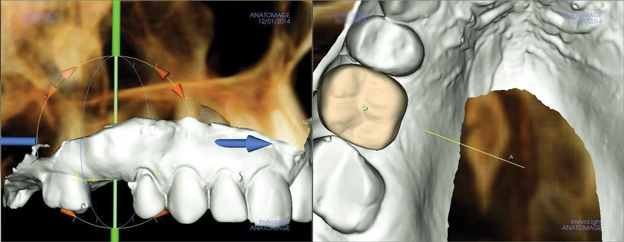

Due to the need for medical treatment for shoulder and neck issues, the patient was delayed in returning to the office for subsequent evaluation. At the 7-month postoperative appointment, the socket was assessed and a panoramic radiograph was taken to evaluate the bone at the planned implant site (Figure 1). The socket was filled with bone that was indistinguishable from the patient's native bone adjacent to the site. Insufficient height to place an implant was noted, which would require a crestal sinus lift prior to implant placement. A cone-beam computed tomography (CBCT) scan was ordered for planning purposes. Planning software was used to properly position a 5.2 x 10 mm implant for placement into the edentulous site, confirming that some elevation of the sinus would be required (Figure 2 and Figure 3). This data was used to order a surgical stent to guide implant placement (Figure 4).

(2.) Virtual planning of the implant to be placed in the edentulous right first molar site.

Figure 2

(3.) Virtual design of the surgical stent to guide the implant placement.

Figure 3

(4.) The surgical stent with metal tube to guide the osteotomy drills during implant placement.

Figure 4